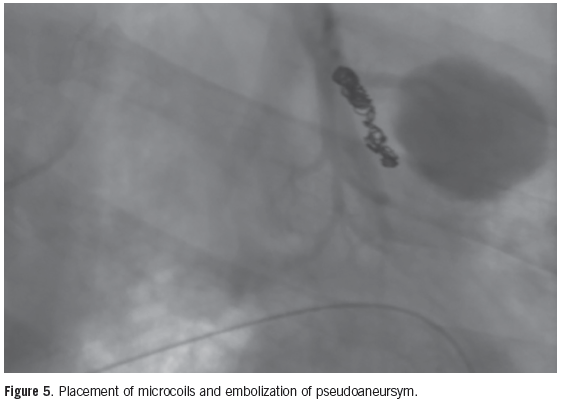

A 49-year-old male presented to the emergency room with hemoptysis, coughing up 400 cc of bright red blood.

A 71-year-old female with no significant past medical history presented to the hospital with sudden onset of massive hemoptysis.

A 46-year-old male presented with a history of intermittently increasing dyspnea on exertion over the past 3 years.